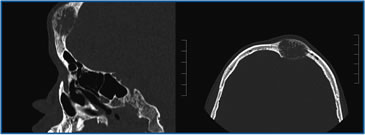

Paciente varón de 14 años de edad, procedente de Antofagasta y con el antecedente de haber presentado a los 8 meses una meningitis bacteriana, quedando con retardo mental leve. Seis meses antes de su hospitalización presenta aumento de volumen duro e indoloro en región frontal y parietal medial del cráneo. Un TAC de cráneo reveló lesiones osteolíticas que se consideraron compatibles con granuloma por presentar I notorio aumento de volúmen de consistencia pétrea, en región cervical izquierda. La ecotomografía tiroidea reveló un nódulo sólido en lóbulo tiroideo izquierdo de 3,2 cm de diámetro mayor con microcalcificaciones, y otro de 1,5 cm de diámetro mayor adyacente a la glándula. Trasladado a nuestro servicio destacó el aumento de volumen pétreo indoloro en región frontal y parietal medial del cráneo, una adenopatía indolora de consistencia aumentada en región cervical izquierda de 2,5 x 1,5 x 3,0 cm. No presentaba neuromas en mucosa oral, y el hábito corporal era normal. Peso 44,5 kg, talla 161 cm (p21) e IMC de 17,2 (p14) (Figura 1). El TAC de cráneo con ventana ósea confirmó la lesión osteolítica a nivel frontal (Figura 2), y el de cuello demostró un nódulo tiroideo izquierdo de aspecto maligno con numerosas adenopatías regionales aisladas, además de lesiones en vértebras cervicales. El TAC de tórax mostró lesiones osteolíticas en vértebras y costillas sin compromiso del parénquima pulmonar y el de abdomen reveló múltiples lesiones focales, hipodensas respecto al resto del parénquima, ubicadas en el segmento posterior del lóbulo hepático derecho, sugerentes de metástasis hepáticas. Cintigrama con Tecnecio 99 y luego un PET-CT con Galio DOTATATE confirma la masa tiroidea con sobreexpresión de receptores de somatostatina asociado a múltiples focos óseos y hepáticos compatibles con metástasis de CMT.

Figura 2. TAC de cráneo con ventana ósea en el que se aprecia una lesión osteolítica en el hueso frontal.